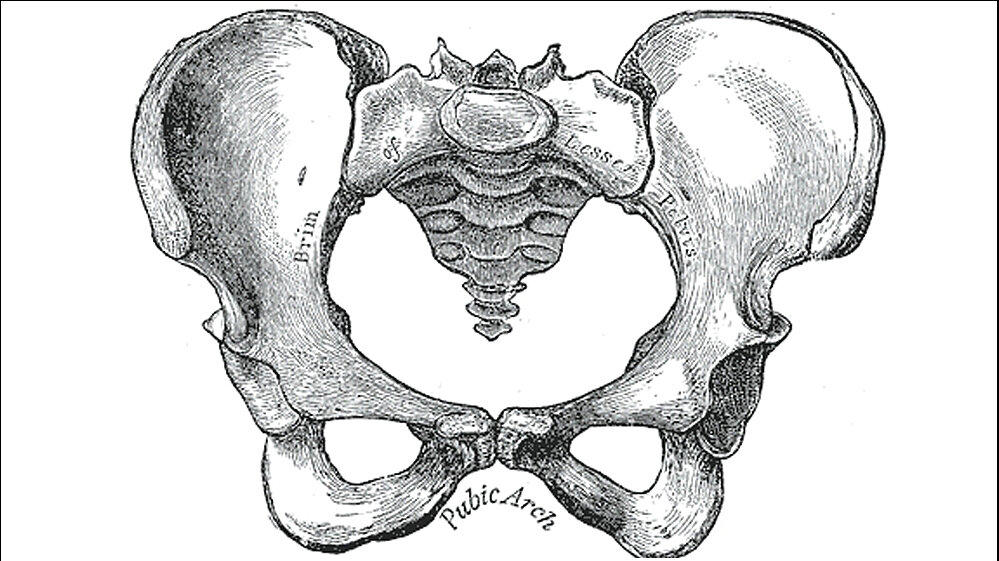

Die erstaunlichen Resultate einer Studie der Universität Zürich legen den Schluss nahe, dass die Hormone in der Pubertät und der Menopause diese Formunterschiede bewirken. Frauen sind in der Körpermitte breiter gebaut als Männer, weil ihr Becken bei der Geburt genug Platz für die großen Köpfe der Babys bieten muss. Warum reicht bei manchen Frauen die Beckenbreite jedoch nicht aus, so dass es zu Schwierigkeiten bei der Geburt kommt? Die gängige Antwort lautet:

Das Becken ist ein evolutionärer Kompromiss zwischen Gebären und Gehen; es kann nicht weiter werden, da sonst die Fortbewegung nicht effizient ist. Diese Hypothese stimmt jedoch nicht ganz: Gemäß neuer Studien sind weite Becken genauso effizient beim Laufen wie enge Becken.

Forscherinnen und Forscher am Anthropologischen Institut der Universität Zürich haben nun neue Erklärungen gefunden. Das Team unter der Leitung von Marcia Ponce de León untersuchte anhand von computertomografischen Daten die Entwicklung des menschlichen Beckens von der Geburt bis ins hohe Alter. Ihr Befund: Bis zur Pubertät sind die Becken beider Geschlechter etwa gleich breit. Während sich das männliche Becken danach gleichmäßig weiterentwickelt, schlägt das weibliche Becken eine neue Richtung ein: Es wird breiter und erreicht im Alter von etwa 25–30 Jahren seine größte Weite. Ab dem 40. Lebensjahr der Frau wird das Becken dann wieder enger.

Die Forscher vermuten, dass diese «Neuprogrammierung» in direktem Zusammenhang mit Änderungen im weiblichen Hormonhaushalt stehen. Während der Pubertät steigt die Konzentration von Östrogen und sinkt erst wieder während der Menopause. Der hohe Hormonspiegel würde demnach nicht nur eine hohe Fruchtbarkeit garantieren, sondern auch dafür sorgen, dass das Becken während dieser Zeit für die Geburt optimiert wird. «Der weibliche Organismus kann offensichtlich das Becken „auf Abruf“ verbreitern und ist nicht einfach einem genetisch festgelegten Entwicklungsprogramm ausgeliefert», erklärt Ponce de León. Gleichzeitig werden die Hormone auch stark von Ernährung und Umwelt beeinflusst.